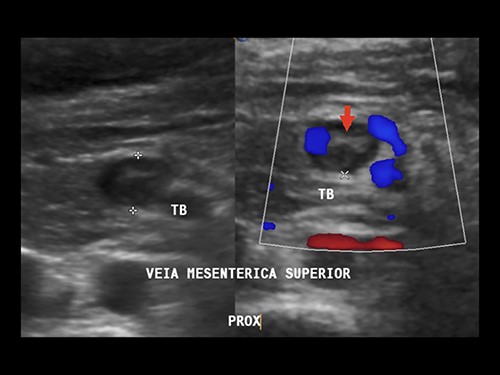

Doppler ultrasonography performed on the first and fifth PODs identified superior and inferior MVT (Fig. 4). Anticoagulation with enoxaparin during the remaining pregnancy and puerperium were prescribed.

Doppler ultrasound showing superior MVT. Arrow: mesenteric vein thrombus.